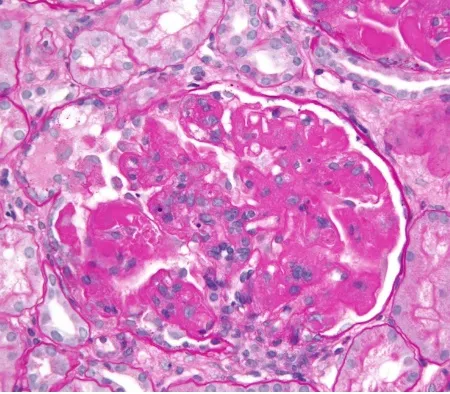

Desescalada de inmunosupresores en la Nefritis Lúpica

Desescalada de inmunosupresores en la Nefritis Lúpica